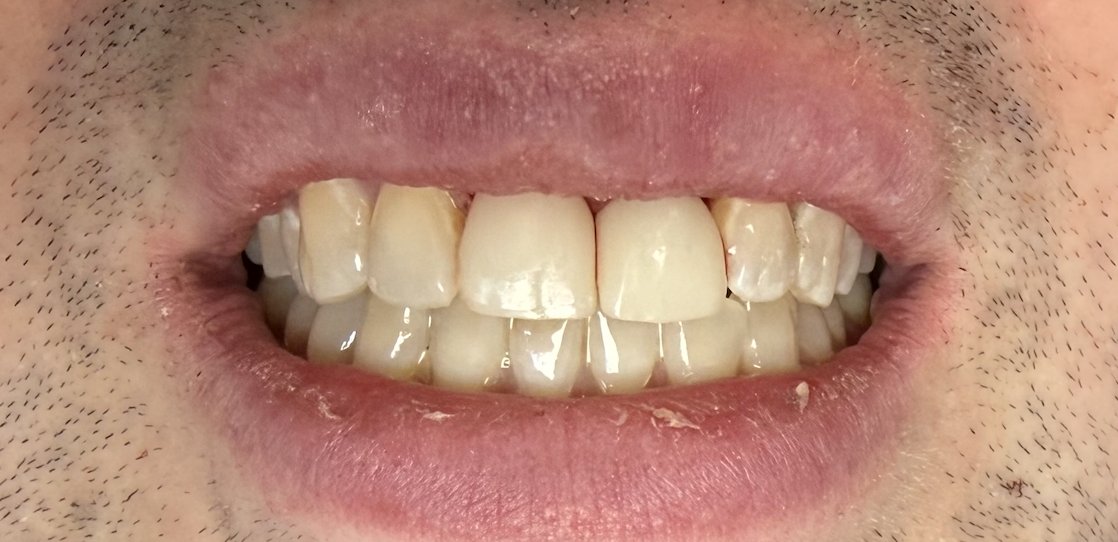

At its core, The Tribeca Dentist is driven by a mission to deliver comprehensive, evidence-based dental care in a warm, welcoming environment conveniently located across from a major government building—ideal for New Yorkers with demanding schedules. The practice offers a full spectrum of services, from preventive cleanings and dental consultations to complex restorative procedures like root canals, surgical extractions, bridges, and cosmetic enhancements. Patients rave about the seamless experience, with testimonials highlighting Dr. Saggese's empathy, efficiency in addressing concerns like cavities, and dedication to follow-up care. One patient noted, 'Dr. Saggese is very caring... fitting me in his schedule during times of need,' while another praised the 'welcoming, professional, and thorough' staff during a cleaning.[1][4]

What truly sets The Tribeca Dentist apart is Dr. Saggese's unique value proposition: full-scope care under one roof, minimizing referrals and ensuring continuity. His bilingual proficiency in English and Italian broadens accessibility, and his personal interests—traveling, socializing, and unwavering passion for dentistry—infuse the practice with a vibrant, empathetic approach. Unlike larger clinics that may feel impersonal, this boutique practice prioritizes individualized treatment plans, leveraging advanced techniques for same-day crowns and full-mouth rehabilitations that combine functionality, health, and aesthetics. The office's modern, clean setup with minimal wait times enhances comfort, while ongoing education keeps treatments at the forefront of innovation.[1][2][5]

Expertise extends beyond Dr. Saggese to include specialists like Dr. Karen Lewkowitz, a Fellow of the American College of Dentists and orthodontic expert from Columbia University and NYU, enabling comprehensive solutions for all ages. Common patient needs—dental emergencies, bridges, cleanings, and implants—are met with precision, protecting bone health and boosting quality of life. Whether restoring a single tooth or overhauling an entire smile, the team delivers natural-looking, durable results that empower patients to eat, speak, and smile confidently.[1][4][5]